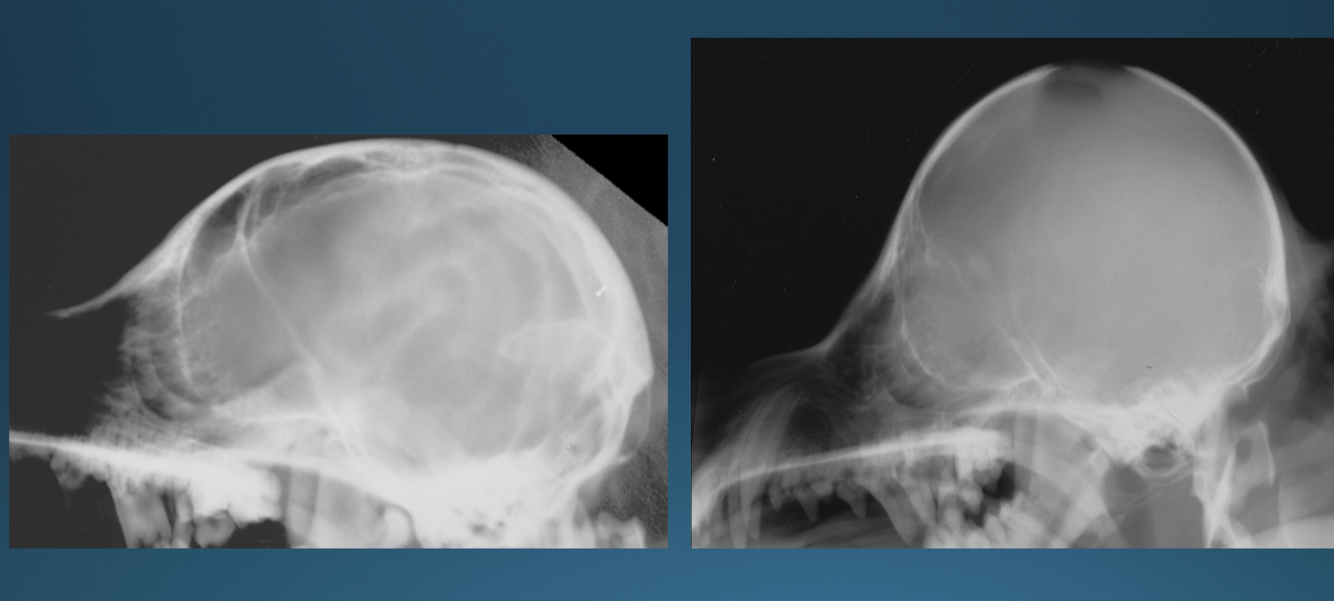

What is shown in these images?

Top Left and Right:

-hydrocephalus with doming of cranial vault

Bottom Left:

-normal